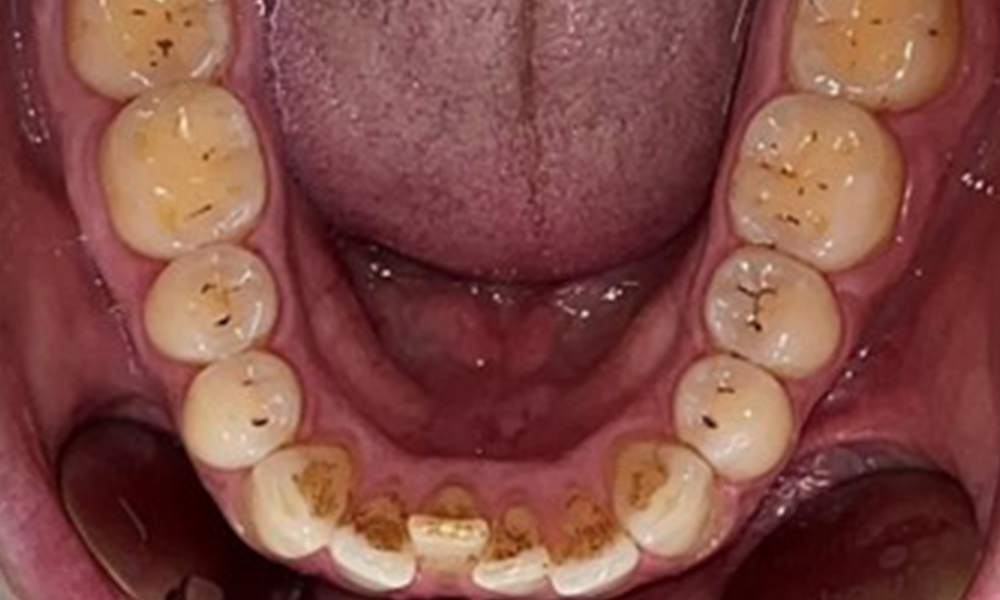

The patient has full dentition with a total of 28 teeth. There were noteworthy erosions and attritions. (Fig. 4, Fig. 5). Due to bruxism, the patient has been wearing a splint with an adjusted bite block at night for many years. The erosions were caused by long-term consumption of isotonic beverages. No periodontal bone loss or active caries were observed.

Full complement of adult teeth with no caries or radiologically recognizable bone loss was observed (Fig. 6). Radiological enamel and cusp loss were particularly evident on 36 and 37.